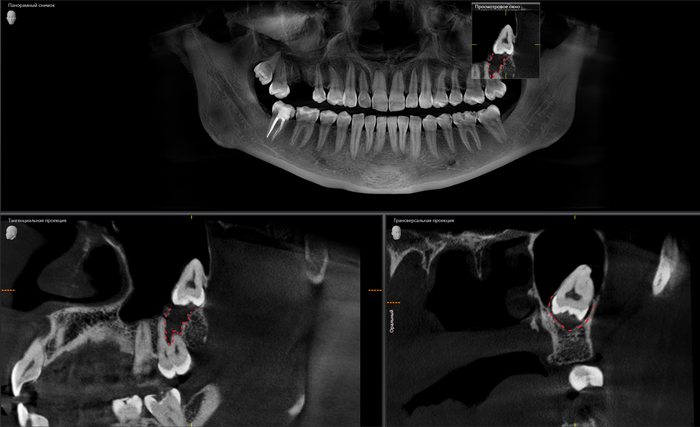

На прием пришла девушка с пожеланием восстановить удаленный ранее в другой клинике зуб на верхней челюсти справа. Ну что ж, без проблем. Направляю пациентку на компьютерную томографию для оценки ситуации. И вдруг я вижу «её» – притаившуюся в пазухе омерзительную восьмерку, которая, противно ухмыляясь, смотрит прямо на меня.

Кроме того, что она сама по себе противная, так еще она успела навредить 7му зубу.

Красным пунктиром отмечено разрастание фолликулярной кисты, которая распространилась в область корней зуба по соседству.

На панорамном снимке, сделанном после имплантации, хорошо видно, насколько высоко и неудачно она располагается: